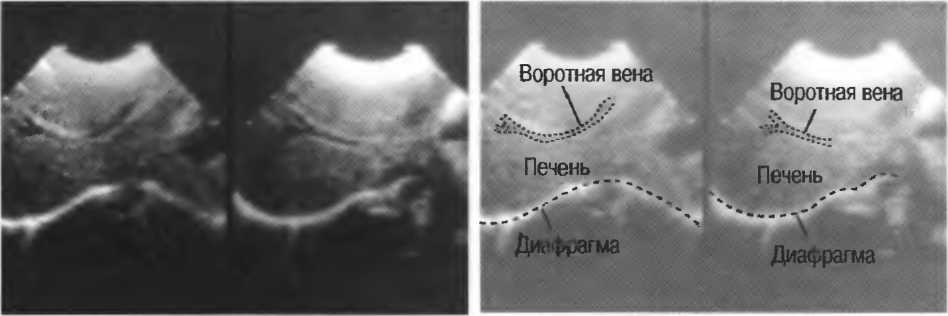

4. У здоровых обследуемых паренхима печени должна быть немного более эхогенна. чем кора рядом расположенной почки (рис. 26).

Рис.26. Продольный срез через печень и правую почку: нормальная паренхима печени более эхогенна, чем паренхима нормальной почки. Это еще один способ проверки качества изображения.